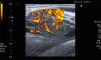

Paciente varo¿n de 53 años, sin antecedentes de interés. Consultó por tumoracio¿n indolora en la parte anterior del antebrazo, sin antecedente traumático. La exploracio¿n confirmó la tumoracio¿n, dura a la palpacio¿n, no desplazable, menor de 1cm. Acudió al gabinete de exploraciones de Reumatología y se practicó una ecografía de partes blandas (Toshiba Aplio®300). Se observó una tumoración redondeada menor de 1cm iso/hipoecogénica en escala de grises, moderadamente delimitada, con un vaso adherido que nutría la lesión (fig. 1). Con Doppler color se observó importante señal, que afecta de manera global a toda la lesión, más intensa en la periferia (figs. 2 y 3). Por signos de sospecha, como la heterogeneidad, la elevada vascularización y la señal Doppler (grado 3) muy importante, se solicitó una RM, que demostró una imagen bien delimitada, redondeada, de 1cm, con hiperseñal en T1, que orientó a una lesión tumoral metastásica (fig. 4).

El caso es útil en la práctica clínica de Reumatología porque: 1) la iconografía permite sospechar la gravedad de una lesión nodular menor de 1cm por su vascularización y heterogeneidad; 2) por destacar la importancia del gabinete de exploraciones de reumatología en el diagnóstico de lesiones tumorales (benignas/malignas) de partes blandas que el reumatólogo no debe eludir; 3) la metástasis cutánea de adenocarcinoma de próstata es muy infrecuente y, en este caso, la ecografía de partes blandas ayudó a orientar el estudio de extensión de la enfermedad neoplásica, y 4) es obligado discriminar las lesiones por su patrón ecográfico y, ante la duda, se debe ampliar el estudio mediante RM4.